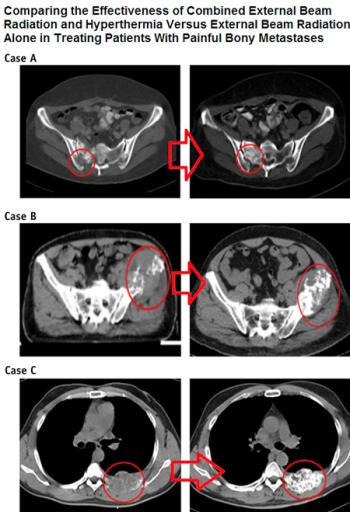

Chi MS, Yang KL, Chang YC, Ko HL, Lin YH, Huang SC, Huang YY, Liao KW, Kondo M, Chi KH. Comparing the Effectiveness of Combined External Beam Radiation and Hyperthermia Versus External Beam Radiation Alone in Treating Patients With Painful Bony Metastases: A Phase 3 Prospective, Randomized, Controlled Trial. Int J Radiat Oncol Biol Phys. 2018 Jan 1;100(1):78-87.

Yapılan bilimsel araştırmada, kemik metastazı olanlarda kanser kitlesinin tamamen ortadan kaldırılma oranları sadece radyoterapi verilmesiyle % 7 iken, radyoterapi yanıan derin doku RF hipertermi verilmesiyle % 38’ e çıkarılmaktadır. Ortalama ağrının olmadığı süre sadece radyoterapi alan hastalarda 55 gün iken, radyoterapiye derin doku RF hipertermi eklenmesiyle çok daha uzun süre ağrı olmadığı saptanmıştır.

Sonuç olarak ağrılı kemik metastazı olan hastalarda radyoterapinin yanına derin doku RF hipertermi eklenmesinin gerek ağrı kontrol süresini gerekse kemikteki kanser kitlesinin tamamen yok edilme şansını belirgin arttırmakta, hastalara daha iyi bir yaşam sunmaktadır.